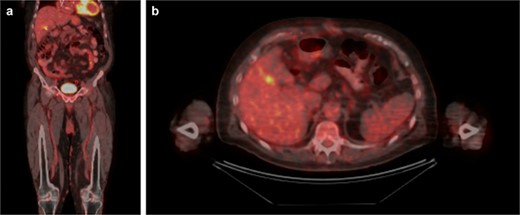

Upon further discussion, the patient reported a history of cutaneous scalp melanoma excision several years prior to his admission. The patient was established with a medical oncologist and underwent positron emission tomography (PET) CT (Fig. 3), with focal uptake seen in the right hepatic lobe adjacent to the gallbladder fossa, concerning for residual disease versus postoperative changes. MR head was performed without evidence of intracranial metastasis. Repeat CT 5 months after resection was without evidence of progressive metastatic disease. This case was presented at an interdisciplinary tumor board conference; the consensus treatment plan was to pursue single-agent immunotherapy.

PET/CT. (A) Coronal and (B) axial slices depicting change status post cholecystectomy and focal uptake in the right hepatic lobe adjacent to the gallbladder fossa